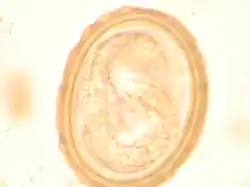

The larva of Ascaris lumbricoides developing in the egg

Ascaris egg, incubation process: The Ascaris egg incubation process consists in placing the egg in a controlled environment, at 26 °C during 28 days, in acidic conditions. This process allows for evaluation of an egg to determine if it is viable or not, by watching the bipartition of the nucleus, and the growth of the larva.

Most diagnoses are made by identifying the appearance of the worm or eggs in feces. Due to the large quantity of eggs laid, diagnose can generally be made using only one or two fecal smears.[29] The diagnosis is usually incidental when the host passes a worm in the stool or vomit. The eggs can be seen in a smear of fresh feces examined on a glass slide under a microscope and there are various techniques to concentrate them first or increase their visibility, such as the ether sedimentation method or the Kato technique. The eggs have a characteristic shape: they are oval with a thick, mamillated shell (covered with rounded mounds or lumps), measuring 35-50 micrometer in diameter and 40–70 in length. During pulmonary disease, larvae may be found in fluids aspirated from the lungs. White blood cells counts may demonstrate peripheral eosinophilia; this is common in many parasitic infections and is not specific to ascariasis. On X-ray, 15–35 cm long filling defects, sometimes with whirled appearance (bolus of worms).